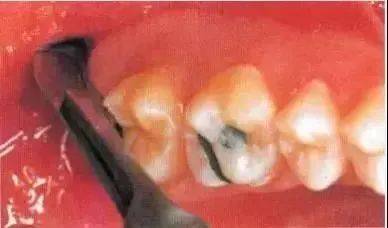

去除颊侧部分骨阻力后,用装在反角机头上的纺锤形车针切割牙冠。用柔韧的小拉钩保护舌侧的黏骨膜(及舌神经)。